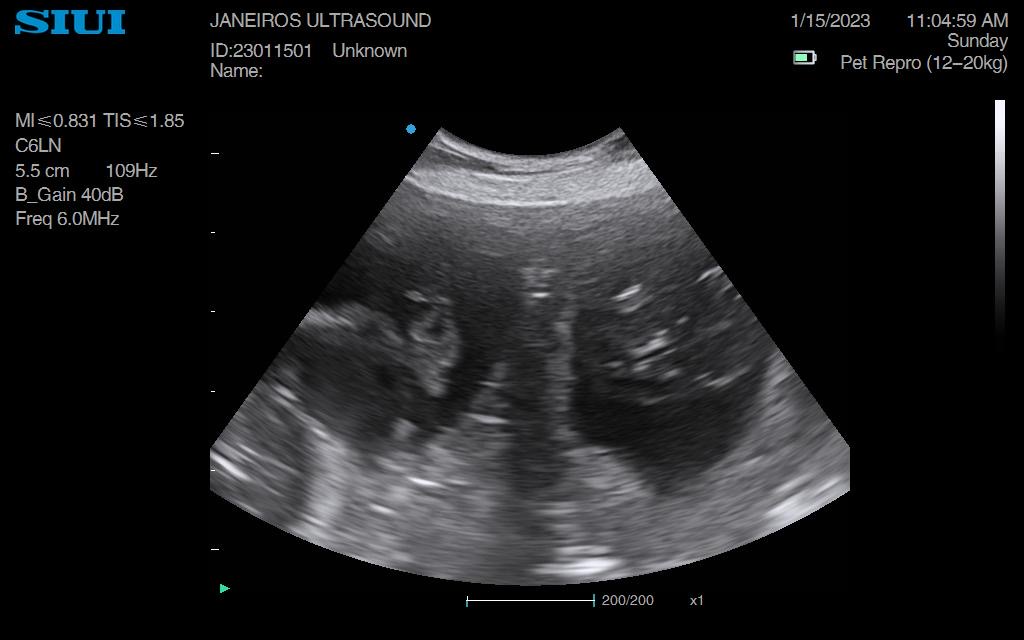

Nala came in for a scan just under 2wks ago. The sacs were tiny so we knew she had only just taken – much later than owner originally thought.

All I could do was confirm pregnancy at this stage and book her in for a rescan. We saw 3 sacks.